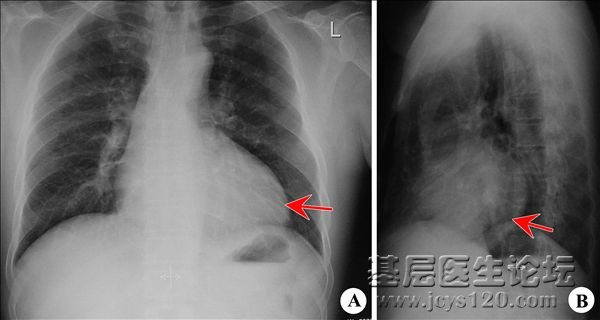

• 患者,男性,82岁,无明显诱因出现活动后气喘。来诊,听诊双肺呼吸音低,未闻及干湿罗音。胸片如下,请看红色线内部分是否正常?只知道应该不是问题,但是不知道怎么解释!  阅读全文>